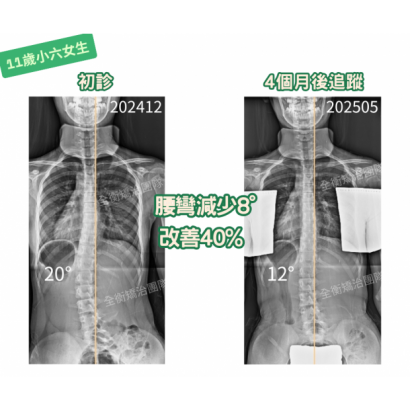

11歲小六女生,4個月改善40%!黃金矯治期真的不能等!

11歲女生,正值青春快速成長期,雖然度數僅20度(中輕度),但惡化風險高,絕不能只觀察!家長毫不猶豫,決定積極治療。

矯治4個月後追蹤,成果喜人

側彎度數從20°→12°,大幅改善40%!

由於骨齡仍年輕,一定要持續追蹤+堅持復健,未來仍有進步潛力!